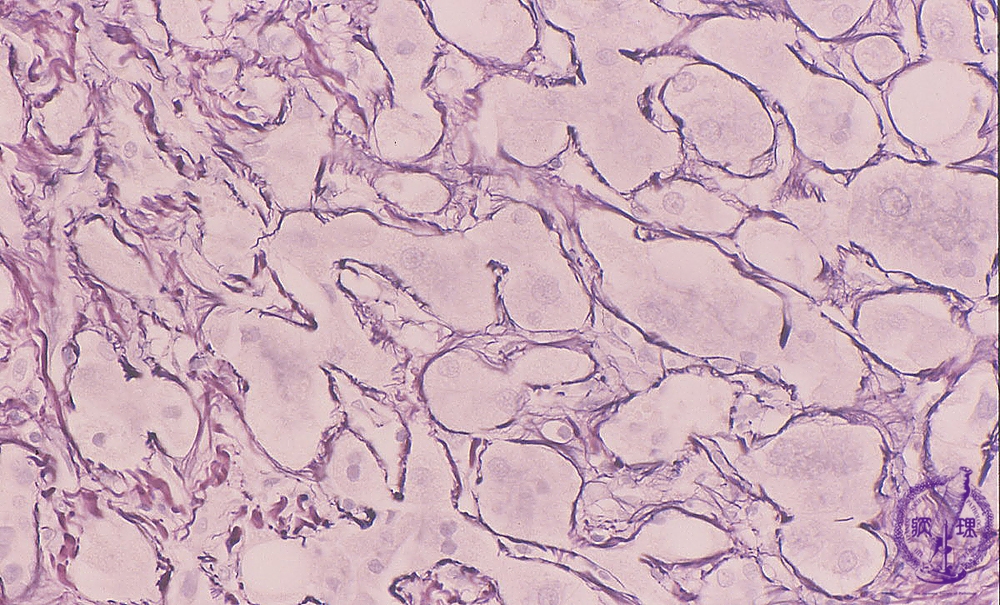

• š(2)Alcoholic hepatitis, cirrhosis

Microscopic image (silver stain, high power): Hepatocytes show distinct centrilobular perisinusoidal fibrosis, consistent with alcoholic steatohepatitis. The hepatocellular architecture is distorted.